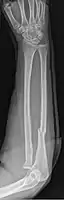

When there is a displaced fracture and also when the radioulnar joints are involved an operation is often performed, using either flexible rods or screws and plates in order to reduce the fracture and immobilise the bone.[2]